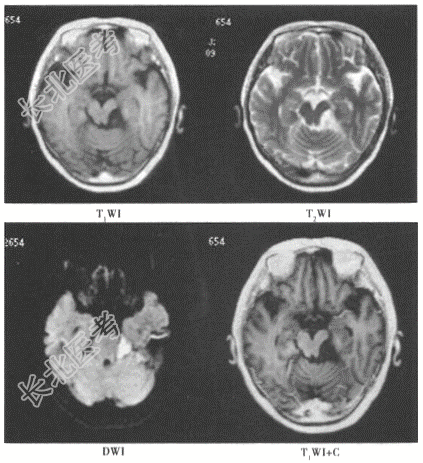

- [材料题] 患者,女,28岁。因左侧面部疼痛1年余入院,影像学检查如下图。

- 简答题1、该患者最有可能的诊断是?

- 简答题2、表皮样囊肿是如何形成的?

- 简答题3、表皮样囊肿的主要症状是什么?

- 简答题4、表皮样囊肿应该如何治疗?